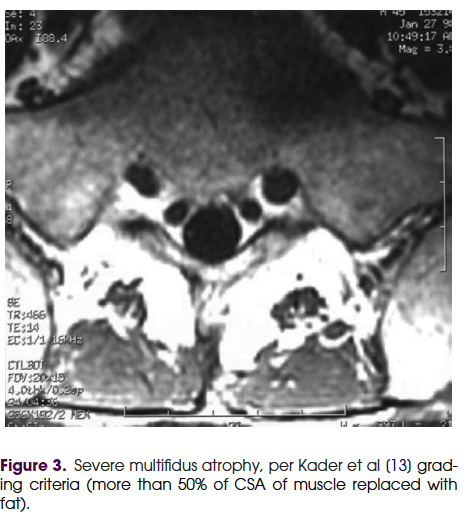

만성요통에서 다열근의 역할에 관한 review논문